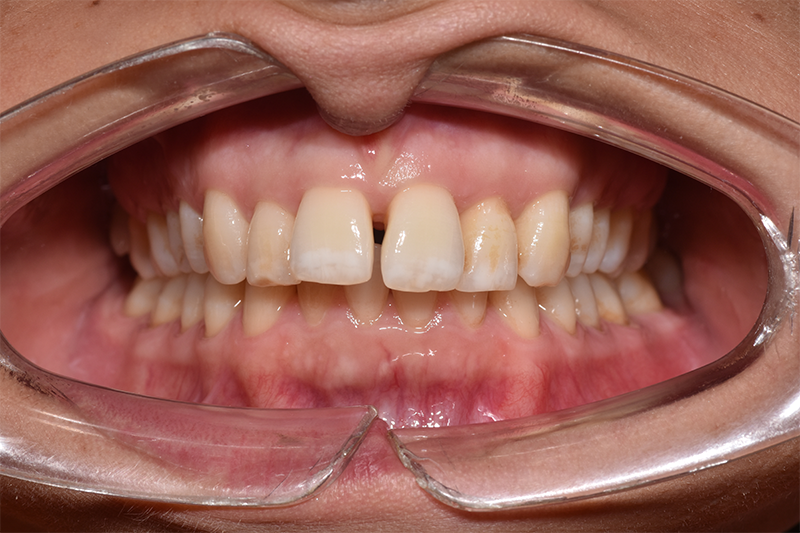

Quando Emanuela, 36 anni, è arrivata nel nostro studio, il suo desiderio era semplice ma importante: chiudere il diastema tra gli incisivi centrali. Non si trattava solo di estetica, ma di sentirsi finalmente a proprio agio con il suo sorriso, senza più quella piccola distanza che la faceva sentire insicura.

In 12 mesi di trattamento Emanuela ha visto il cambiamento giorno dopo giorno, fino a raggiungere il risultato tanto desiderato.

PRIMA